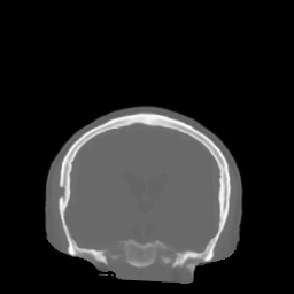

Model-based treatment planning for transcranial ultrasound therapy typically involves mapping the acoustic properties of the skull from an x-ray computed tomography (CT) image of the head. Here, three methods for generating pseudo-CT images from magnetic resonance (MR) images were compared as an alternative to CT. A convolutional neural network (U-Net) was trained on paired MR-CT images to generate pseudo-CT images from either T1-weighted or zero-echo time (ZTE) MR images (denoted tCT and zCT, respectively). A direct mapping from ZTE to pseudo-CT was also implemented (denoted cCT). When comparing the pseudo-CT and ground truth CT images for the test set, the mean absolute error was 133, 83, and 145 Hounsfield units (HU) across the whole head, and 398, 222, and 336 HU within the skull for the tCT, zCT, and cCT images, respectively. Ultrasound simulations were also performed using the generated pseudo-CT images and compared to simulations based on CT. An annular array transducer was used targeting the visual or motor cortex. The mean differences in the simulated focal pressure, focal position, and focal volume were 9.9%, 1.5 mm, and 15.1% for simulations based on the tCT images, 5.7%, 0.6 mm, and 5.7% for the zCT, and 6.7%, 0.9 mm, and 12.1% for the cCT. The improved results for images mapped from ZTE highlight the advantage of using imaging sequences which improve contrast of the skull bone. Overall, these results demonstrate that acoustic simulations based on MR images can give comparable accuracy to those based on CT.